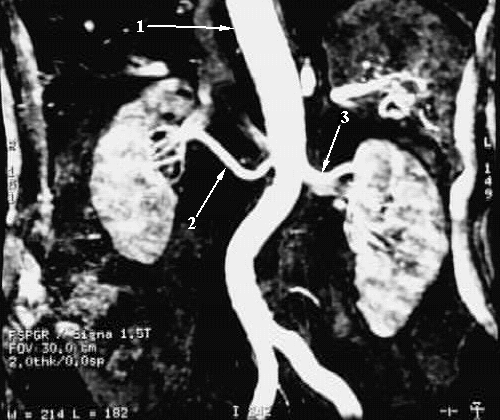

Abdomen - Kidney MR Angiogram

1. Abdominal Aorta

2. Right Renal Artery

3. Left Renal Artery